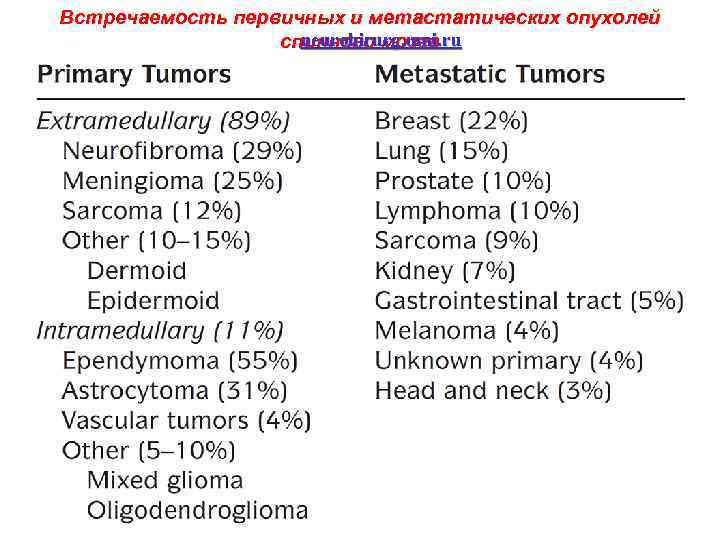

Встречаемость первичных и метастатических опухолей neurohirurg. umi. ru спинного мозга 26